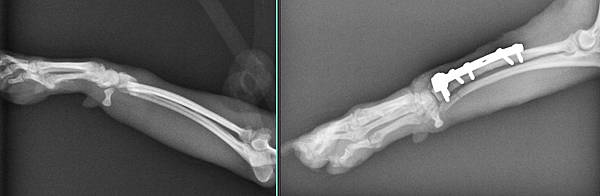

漿漿是一位很活潑的吉娃娃小朋友

右手跛行

檢查發現骨折

手術修復

很快恢復走跳的能力